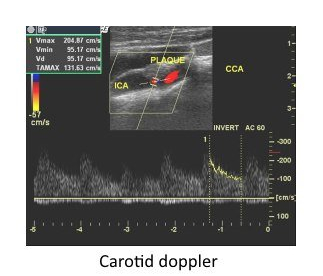

Carotid Color Doppler: Carotid Doppler is specifically meant for assessment of blood vessels that supply the brain. Carotid arteries are the major vessels which carry blood to the brain.